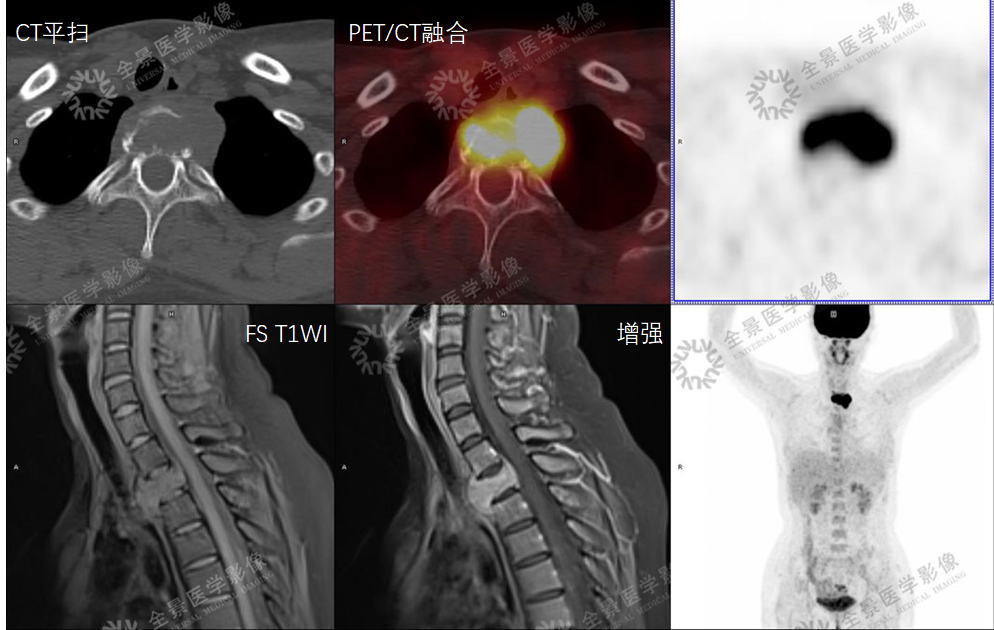

骨关节

案例 :骨巨细胞瘤

T2WI不均匀等信号,

PET/CT显示:T3骨质破坏并周围软组织肿块形成,FDG明显摄取增高。

增强扫描明显强化